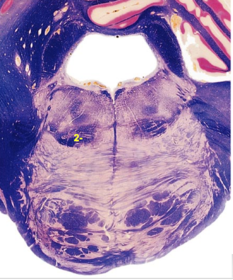

| Hypoglossal nucleus | |

| Hypoglossal nerve | |

| Dorsal motor nucleus of X | |

| Nucleus ambiguus | |

| Solitary tract | |

| Solitary nucleus | |

| ALS | |

| Medial lemniscus | |

| Medial longitudinal fasciculus | |

| Spinal tract of V | |

| Spinal nucleus of V | |

| Lateral (external, accessory) cuneate nucleus | |

| Medullary pyramids | |